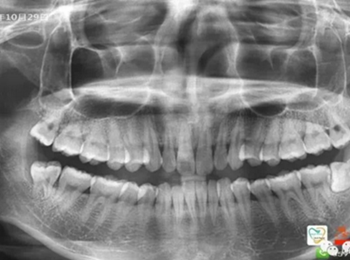

由于智齒的生長位置特殊,導(dǎo)致了拔除難易不同,如智齒出現(xiàn)橫著長或者靠近牙神經(jīng)的話,則難度會較高,一般人只需拍個口腔全景片,但相對于智齒靠近神經(jīng)管的情況,還可能需要拍CT,這都很考驗牙醫(yī)的技術(shù)。

拔牙非小事,請不要拿成本衡量牙醫(yī)的價值!

下面這兩張圖,據(jù)說拔牙費時1.5小時,收費14000元。